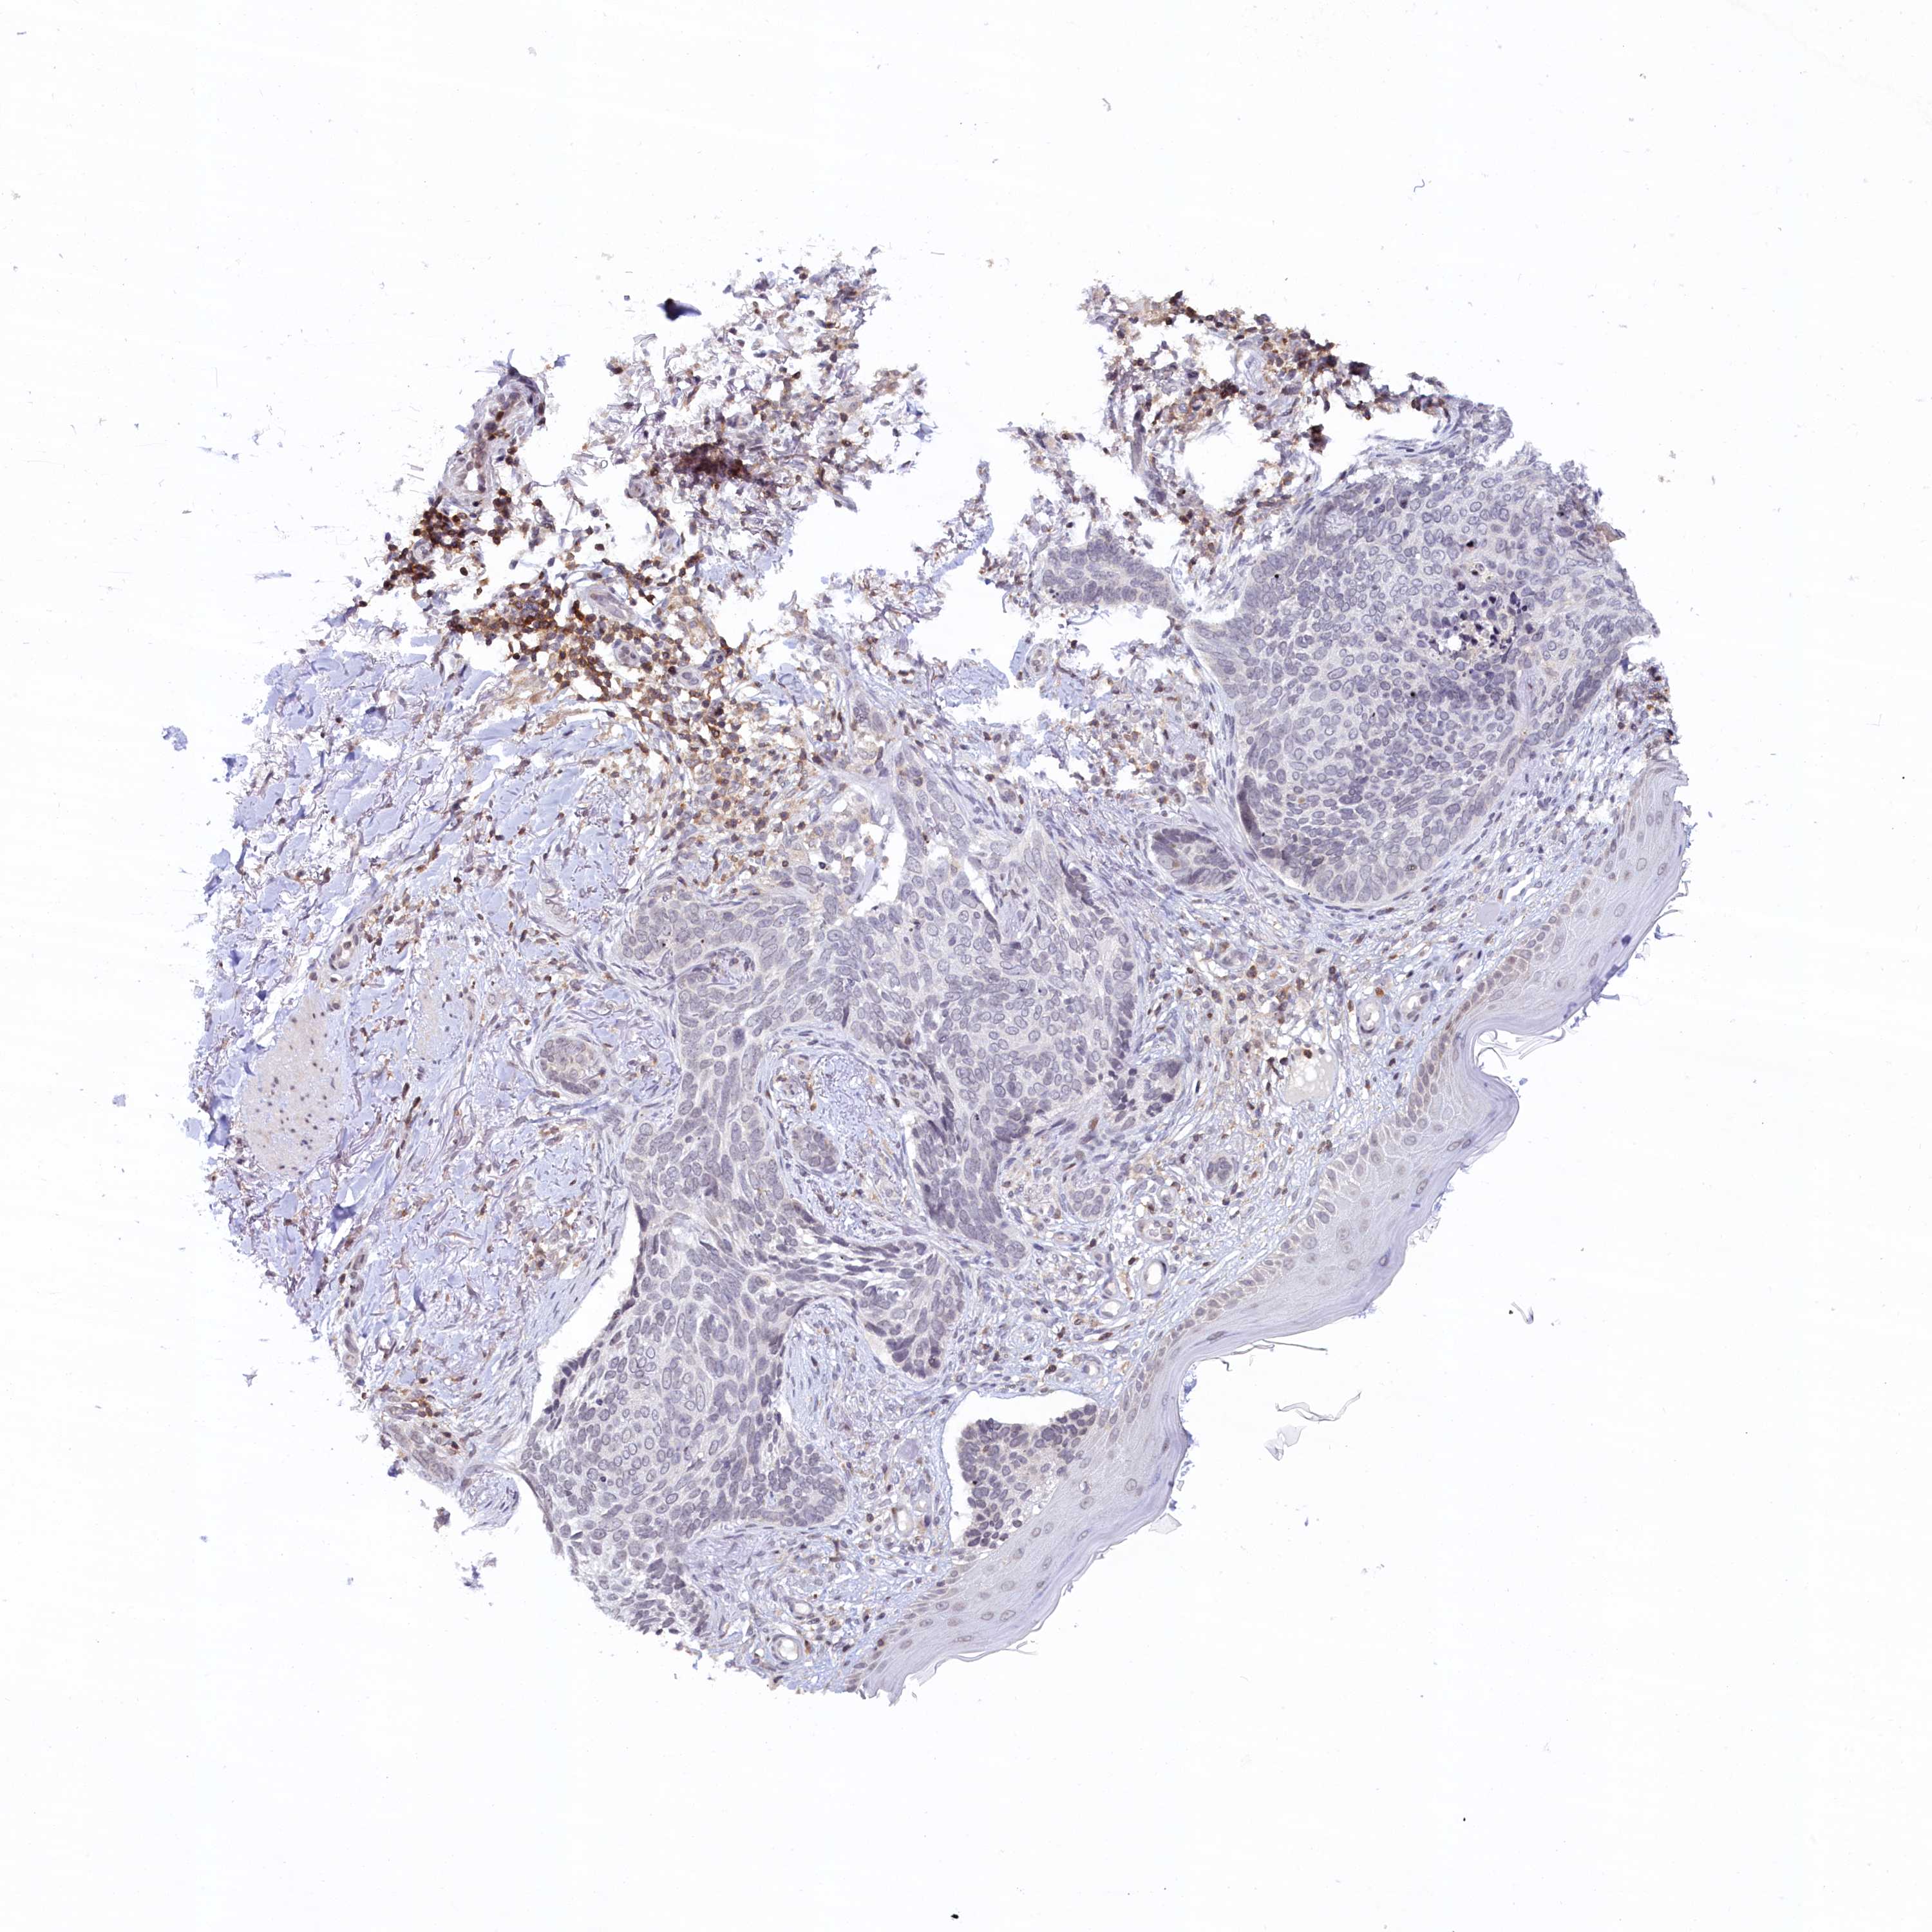

SKIN CANCER - Protein expressioni

A mouse-over function shows sample information and annotation data. Click on an image to view it in a full screen mode. Samples can be filtered based on level of antibody staining by selecting one or several of the following categories: high, medium, low and not detected. The assay and annotation is described here.

Each image is clickable and will lead to virtual microscopy that enables deeper exploration of all samples and also displays staining intensity scores, fraction scores and subcellular localization as well as patient and tissue information for each sample.

Antibody HPA026796

Staining

High

Medium

Low

Not detected

Intensity

Strong

Moderate

Weak

Negative

Quantity

>75%

75%-25%

<25%

None

Location

Nuclear

Cytoplasmic/membranous

Cytoplasmic/membranous,nuclear

Basal cell carcinoma